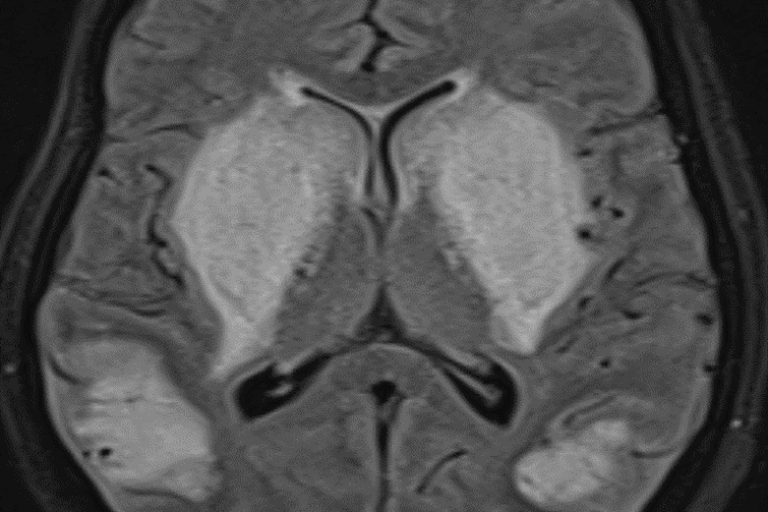

Advanced diagnosis and management of seizures using EEG, medications, and lifestyle guidance to achieve better control and improve long-term brain health.

Epilepsy & Seizures